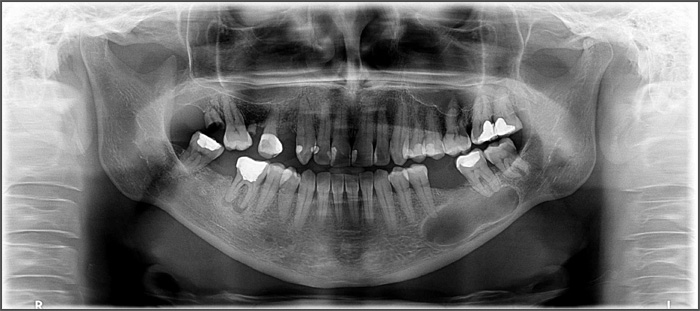

Jaw cysts grow very slowly and in the vast majority of cases patients do not have any symptoms. They are often discovered as an incidental finding when x-rays are taken to look for other things. If the cyst becomes infected they can become painful. Cysts can grow very large and can cause damage to adjacent teeth which can become loose. Very large cysts can also expand the jaw and very occasionally can be so big that they can weaken the jaw leading to a fracture.

What will happen at the consultation?

The consultation is a very important part of the treatment, it is an opportunity to meet the consultant and team that will be looking after you. Following an examination and x-rays the consultant will be able to establish a diagnosis. Sometimes when cysts are large or close to other structures it may be necessary to obtain a CT scan which gives a 3-D view and aids the surgery. The consultant will explain what the surgery will entail and what to expect afterwards.